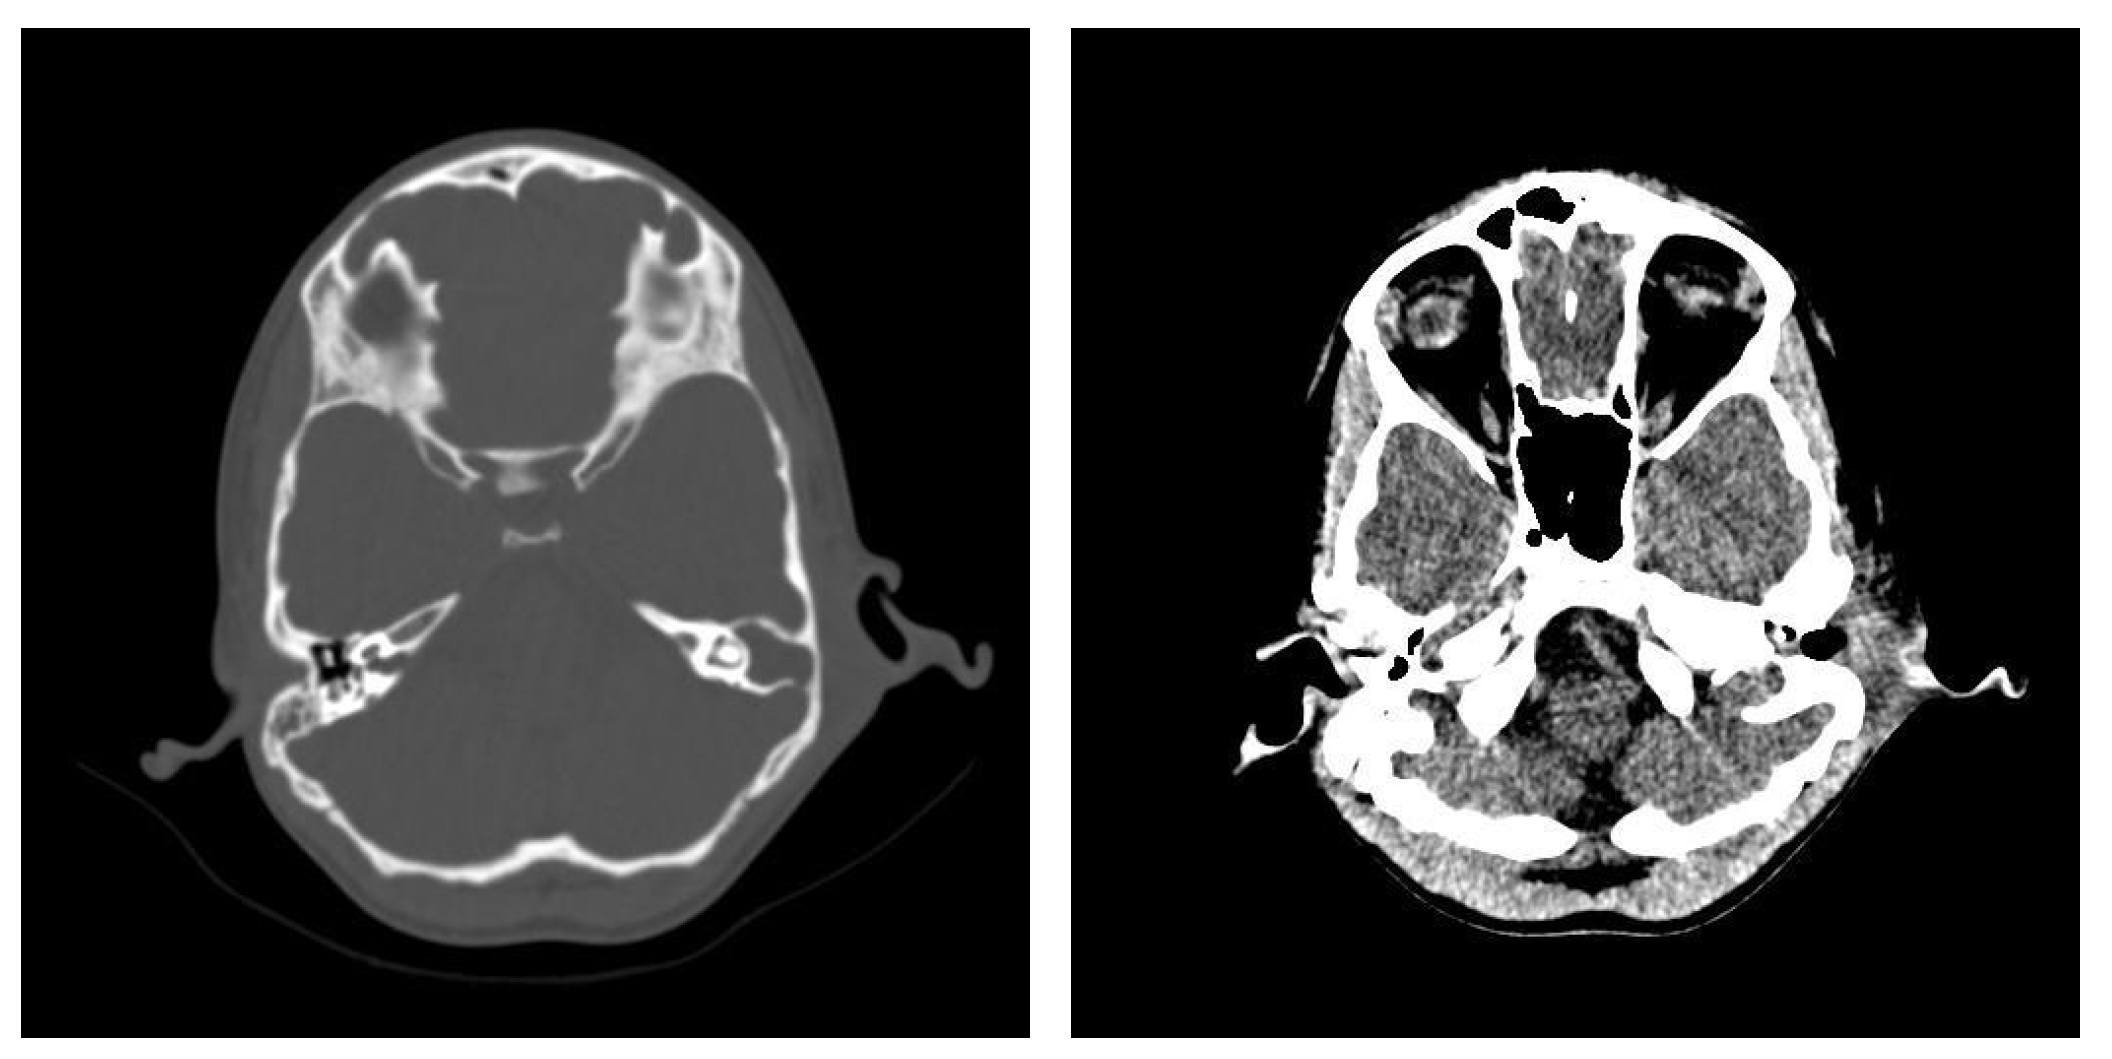

3.1.2. Computed Tomography and Magnetic Resonance Imaging

| CT Aspects | Number of Patients | Percentage |

|---|---|---|

| Fluid accumulation | 168 | 100% |

| Osteolysis | 152 | 90.47% |

| Osteocondensations | 128 | 76.19% |

| Cholesteatoma | 48 | 28.57% |

| Exocranial extensions | 48 | 28.57% |

| Intracranial extensions | 24 | 14.28% |

| Changes to the external auditory canal | 68 | 40.47% |

| Ossicular chain damage | 144 | 85.71% |